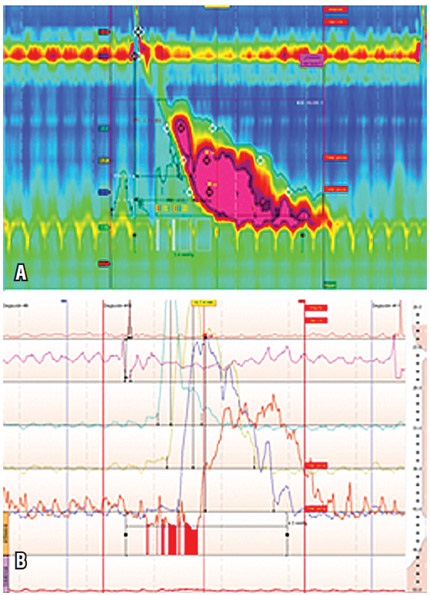

Hombre de 72 años con síntomas típicos de ERGE, quien además venía cursando con disfagia ocasional para sólidos. Tenía estudios con EVDA sin anormalidades y un esofagograma con bario que demostró cambios por presbiesófago y aparente divertículo esofágico. En el estudio con MAR se encontraron 3 ondas con ICD mayor de 5000 mm Hg/cm/s, una de ellas con ICD en 8809 mm Hg/cm/s. Cabe destacar que se observaron, además, 6 ondas multipico, hallazgo que refuerza el diagnóstico del esófago en martillo neumático (tablas 1 y 2; figura 3).